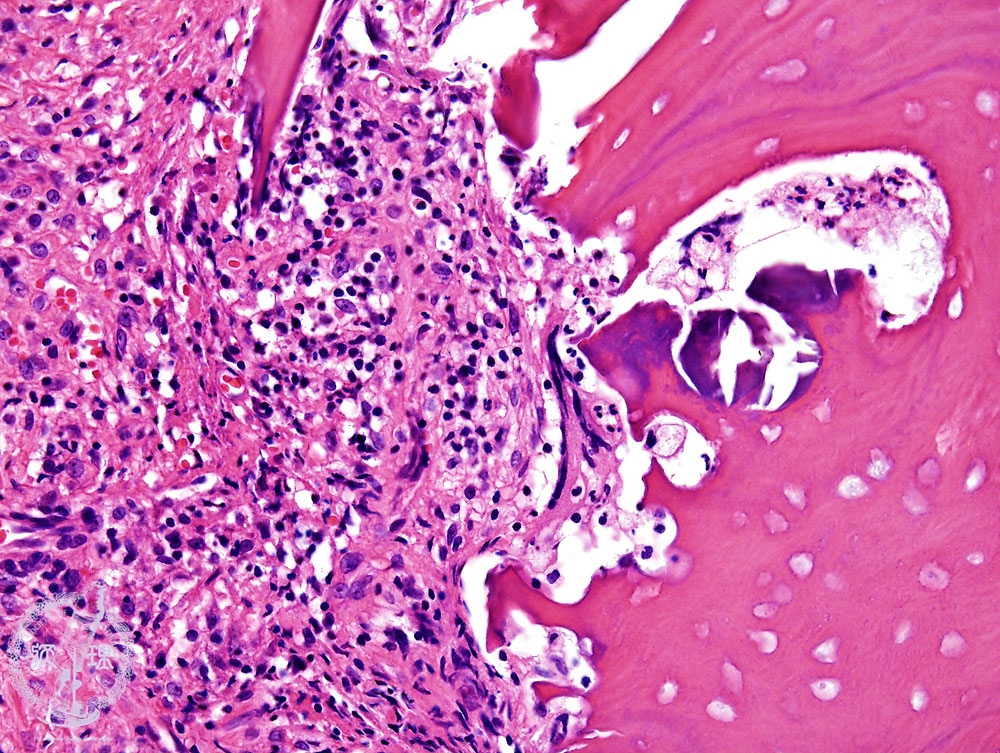

- (5)Suppurative osteomyelitis

Microscopic view (HE: high power view):Infiltration of neutrophils and fibrosis are seen. Bone is necrotic, with disappearance of the nuclei within the lacuna of the bone.